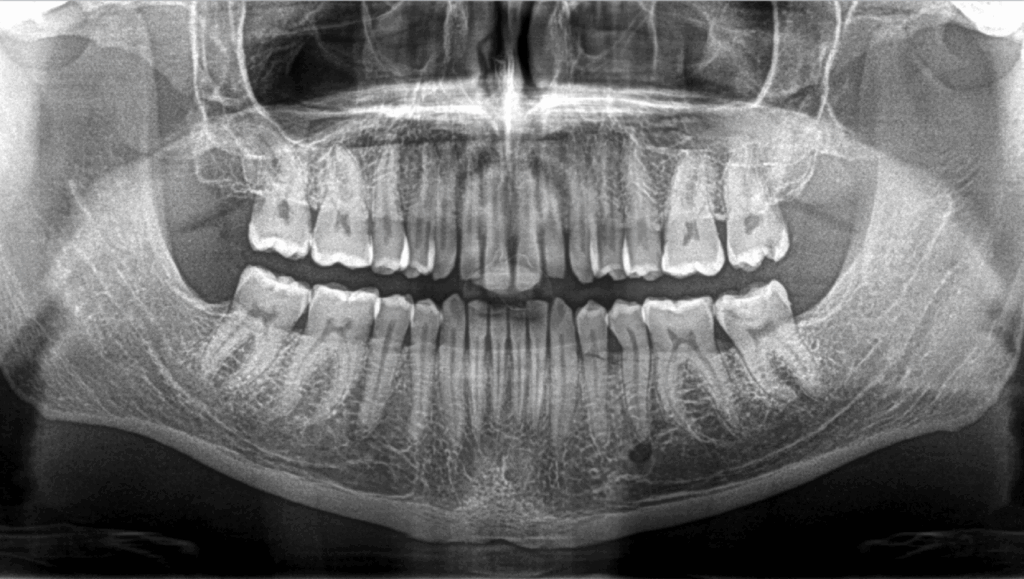

🔍 Douleur secteur 3, à la percussion, à la mastication, 𝐬𝐞𝐧𝐬𝐚𝐭𝐢𝐨𝐧 𝐝𝐞 𝐝𝐞𝐧𝐭 𝐥𝐨𝐧𝐠𝐮𝐞.

Quelle pourrait être l’étiologie de la 𝐧𝐞́𝐜𝐫𝐨𝐬𝐞 𝐩𝐮𝐥𝐩𝐚𝐢𝐫𝐞 et de la 𝐩𝐚𝐫𝐨𝐝𝐨𝐧𝐭𝐢𝐭𝐞 𝐚𝐩𝐢𝐜𝐚𝐥𝐞 𝐬𝐲𝐦𝐩𝐭𝐨𝐦𝐚𝐭𝐢𝐪𝐮𝐞 de cette 35 ?

🦷 L’image radioclaire péri-apicale est le 𝐟𝐨𝐫𝐚𝐦𝐞𝐧 𝐦𝐞𝐧𝐭𝐨𝐧𝐧𝐢𝐞𝐫.

🦷 Les symptômes proviennent de la dent n°34, 𝐟𝐫𝐚𝐜𝐭𝐮𝐫𝐞́𝐞.